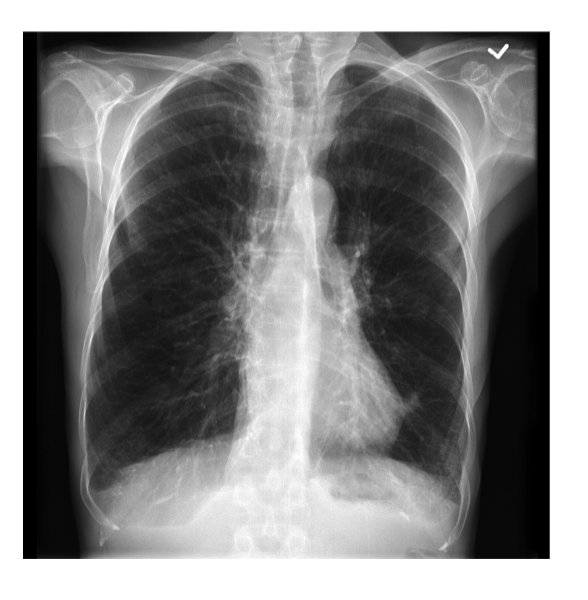

what is pictured/what is occurring with the lungs in the image attached?

hyperinflation of the lungs

how might COPD present on CXRs?

see hyperexpansion (more than 10 ribs seen, barrel chest), flattened diaphragm, cardiomegaly, cystic changes, irregular air pockets, costophrenic angle changes